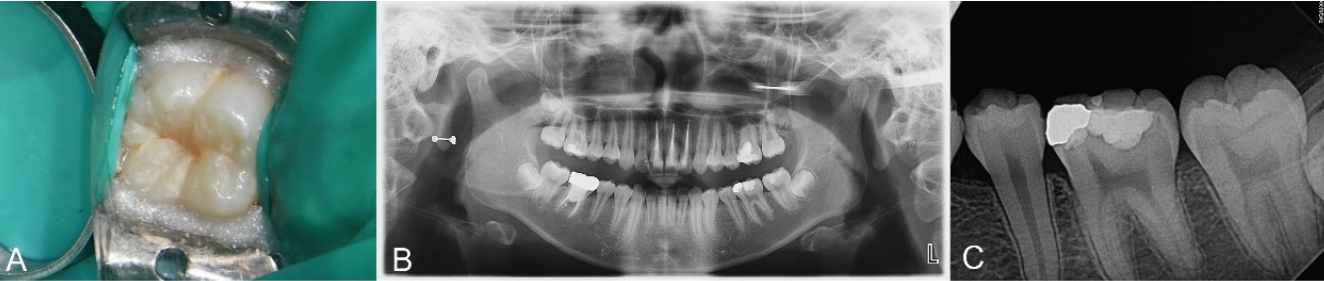

치료 전 1:100000 epinephrine을 포함하는 2% Lidocaine(Yuhan Corp, Seoul, Korea)으로 우측 하악 구치부 전달마취를 시행하였다. 러버댐을 이용하여 격리를 시행하고 주수 하에 Prophy brush를 사용해 교합면을 세정하였다. 이후 유동형 복합레진(Tetric N-Flow, Ivoclar Vivadent, Schaan, Liechtenstein) 을 교합면에 적용하고 마이크로브러시의 팁을 손잡이로 사용하기 위해 복합레진에 위치시킨 뒤 광중합하여 스탬프를 형성하였다. 그 후, 일반적인 와동 형성 프로토콜에 따라 우식 제거를 시행하였다. round diamond bur를 이용하여 고속 핸드피스로 주수 하에 우식을 제거하였다. 법랑질 먼저 10초간 35% phosphoric acid로 산부식한 뒤 상아질에 10초간 추가로 산부식하고 수세하였다(Fig. 4A). 약하게 공기를 분사하여 수분을 제거한 뒤 3-step etch-and-rinse system인 Adper Scotchbond Multi-Purpose Bond의 primer를 microbrush로 5초간 도포하고, 공기 분사 후 adhesive를 microbrush로 5초간 도포하고 공기 분사한 뒤 LED 광중합기로 10초간 광중합하였다. 이후 Microhybrid계 복합레진인 Filtek Z250를 이용해 교합면에서 2mm 아래까지 수복하고 20초간 광중합하였다. 최종 복합레진 적층 전 테플론 테이프를 교합면에 덮고 제작한 스탬프를 정밀하게 위치시켜 가볍게 압력을 주었다(Fig. 4B). 스탬프 및 테플론 테이프를 조심스럽게 제거한 뒤 과잉 재료를 레진 기구로 정리하고 광중합하였다(Fig. 4C). 교합지와 심스탁을 이용한 교합 검사 후 교합 조정을 시행하였다. Sof-lex spiral로 수복물 연마를 시행하였다.

Fig. 4.

A. Selective etching iss done with 37% phosphoric acid. B. Stamp is placed and gently pressed. C. Photograph after applying stamp on teeth. D. Postoperative periapical radiograph.